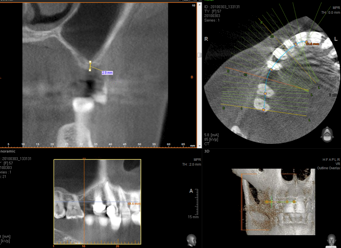

soit au niveau des maxillaires supérieurs à l'intérieur du sinus maxillaire (intervention appelée : "soulevé ou greffe de sinus") comme cela :